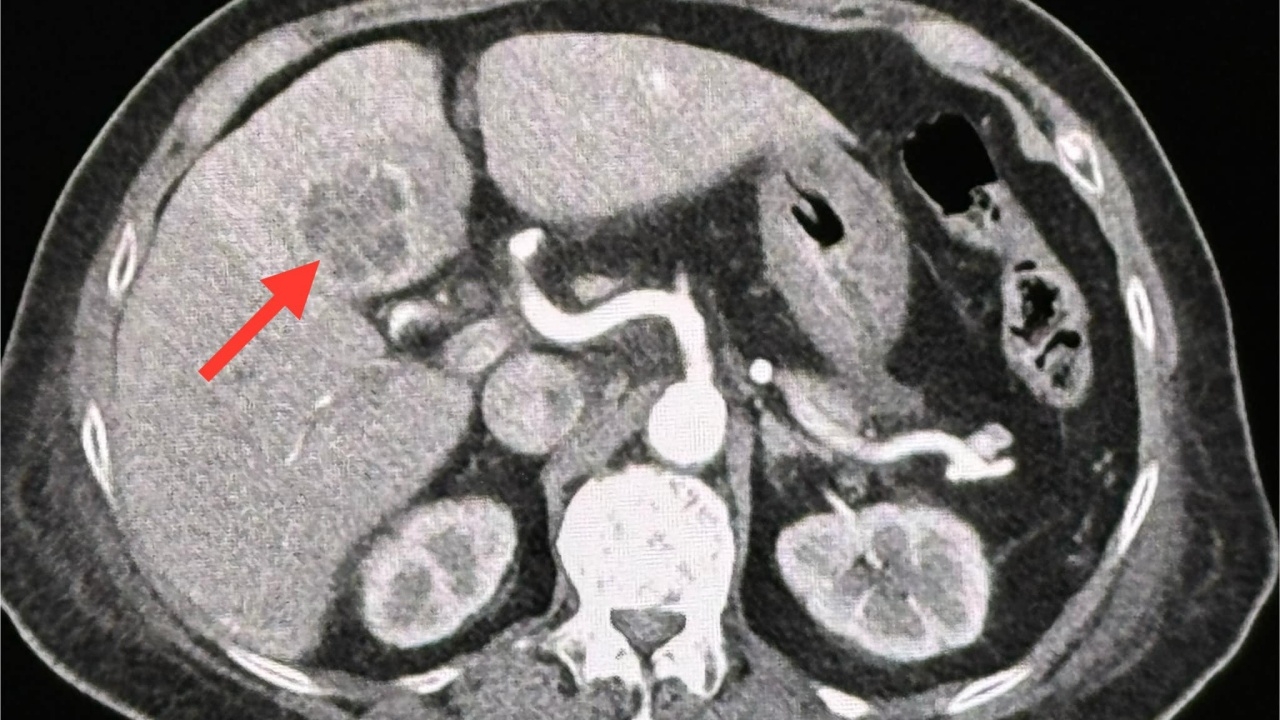

ทำอัลตราซาวนด์ช่องท้องด้านบน พบก้อนในตับข้างซ้ายขนาด 2.8 × 2.4 × 2.4 เซนติเมตร ส่งเลือดเพาะเชื้อ ขึ้นเชื้อแบคทีเรีย Klebsiella pneumoniae ทำคอมพิวเตอร์ช่องท้อง 2 วันต่อมา พบก้อนขนาด 3.3 × 3.3 × 2.8 ซม.ในตับข้างซ้าย เข้าได้กับฝีในตับ วินิจฉัย : ฝีในตับจากเชื้อแบคทีเรีย Klebsiella pneumoniae และติดเชื้อในกระแสเลือด ทำให้ช็อก ความดันต่ำ